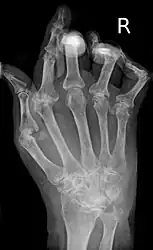

| A hand severely affected by rheumatoid arthritis. This degree of swelling and deformation does not typically occur with current treatment. | |

As the pathology progresses the inflammatory activity leads to tendon tethering and erosion and destruction of the joint surface, which impairs range of movement and leads to deformity. The fingers may suffer from almost any deformity depending on which joints are most involved. Specific deformities, which also occur in osteoarthritis, include ulnar deviation, boutonniere deformity (also "buttonhole deformity", flexion of proximal interphalangeal joint and extension of distal interphalangeal joint of the hand), swan neck deformity (hyperextension at proximal interphalangeal joint and flexion at distal interphalangeal joint) and "Z-thumb." "Z-thumb" or "Z-deformity" consists of hyperextension of the interphalangeal joint, fixed flexion and subluxation of the metacarpophalangeal joint and gives a "Z" appearance to the thumb.[18]: 1098 The hammer toe deformity may be seen. In the worst case, joints are known as arthritis mutilans due to the mutilating nature of the deformities.[22]